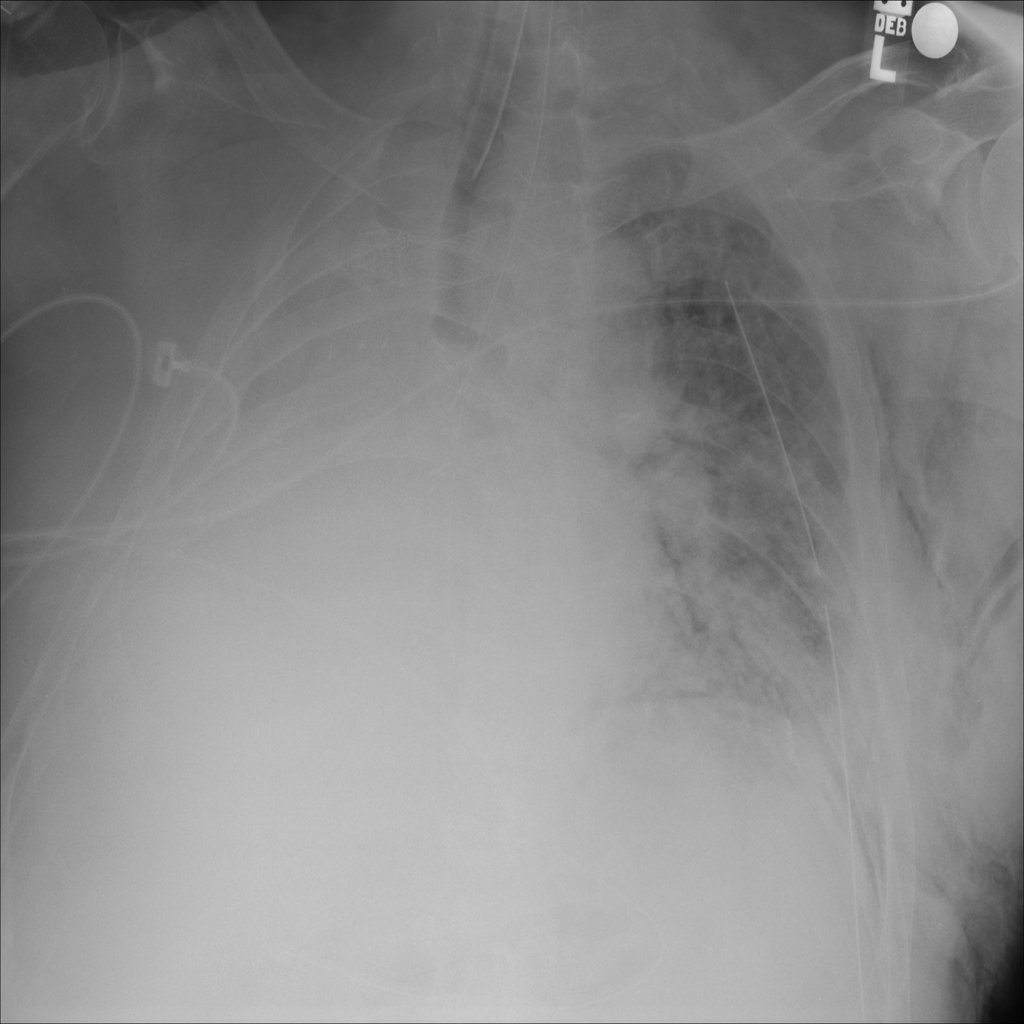

PAT-BDEB · IMG-001Emphysema

PAT-BDEB · IMG-001

AP